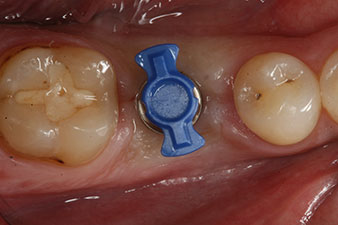

SmartPeg

Figura 4: Poste de medición atornillado SmartPeg para determinar el cociente de estabilidad del implante con el módulo Osstell ISQ de W&H.

El torque en el momento de la carga mecánica fue de 43 Ncm. Asimismo, después de atornillar un poste de medición especial adaptado al sistema de implante (SmartPeg), el valor ISQ se determinó con la sonda del módulo Osstell ISQ de W&H.

sonda de medición

Figura 6: Diez semanas después, fue posible retirar de nuevo el pilar de cicatrización que se había incorporado de forma provisional. En la dirección linguo-bucal se midió un valor ISQ prácticamente inalterado de 63 (sonda de medición sin contacto a una distancia de 2 a 3 mm).

Dos meses después, el implante se expuso y se introdujo un pilar de cicatrización (no hay figura).

Después de la cicatrización de los tejidos blandos, se volvió a determinar la estabilidad del implante antes de continuar con el tratamiento protésico.